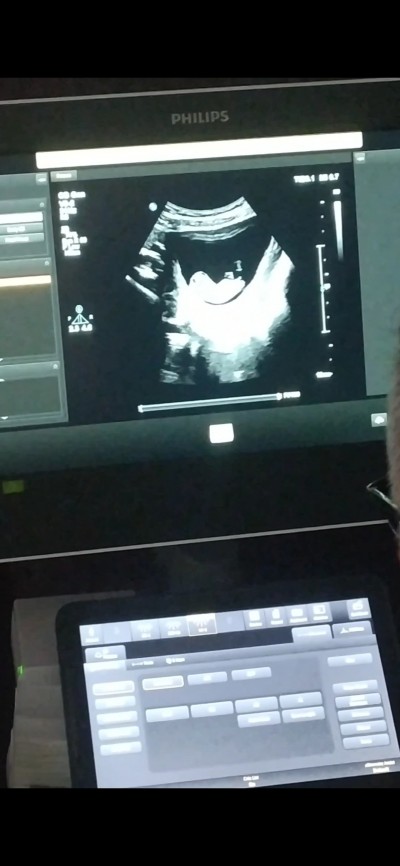

Merhaba kızlar cinseyetini merak ediyorum tahminler var bakalım siz ne görüyorsunuz tabiki kız

erkek farketmez Allah'ın takdiri ne verirse baş göz üstüne ama ilk gebeliğim merak etmiyor değilim

Orda bir çıkıntı var ama erkek sanırım

Çıkıntı sanırım ayağı  bugün tam 12 haftalık olduk gittiğimde 11 haftalıktı

Kız orda ben 'erkegim anneeee diye bağırıyor" :P sağlıkla kucağına al insAllqh

Aslında video var ama huraya yüklenmiyor çıkıntı sanırım ayağı en altta küçük bi şişlik var acaba erkek mi  teşekkür ederim bu arada yorumunuz için

Ayağının altında çıkıntı pipiye benziyor canım yani

Erkek olsaydı doktorunuz söylerdi genelde daha erken belli oluyor. Benim 11.haftada göstermişti oğlum

askim bu bebis ben erkegim diyee bagiriyo :)

Erkek gibi bence